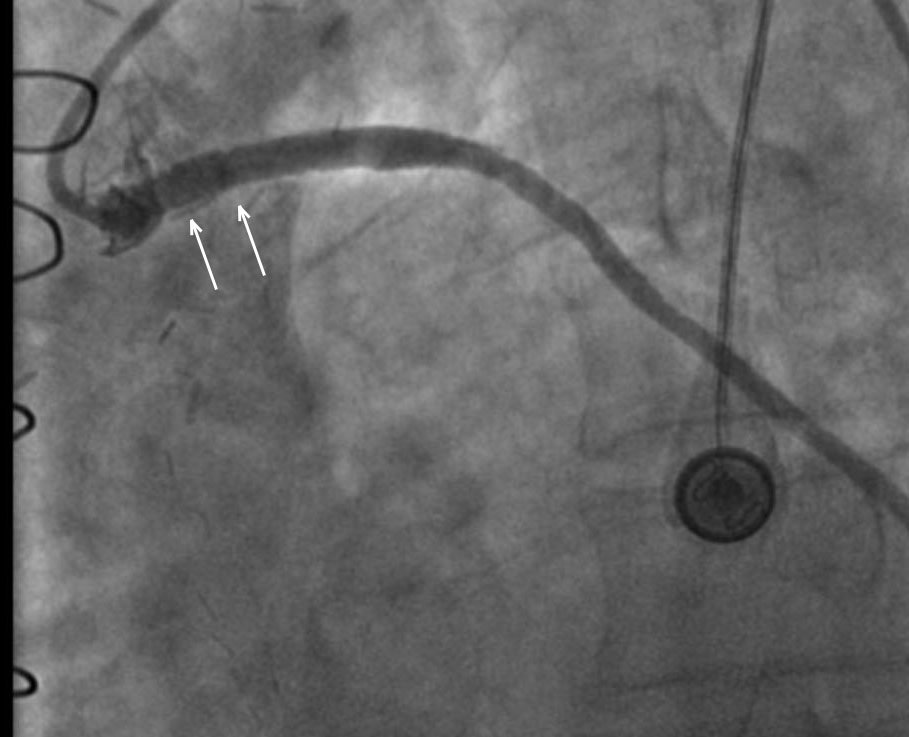

Стентирование позвоночной артерии. Что такое стентирование пмжв лка. Операция на сердце стентирование. Стентирование коронарных артерий. Чкв баллонная ангиопластика.

Стентирование устья пмжв. Стенозирование коронарной артерии. Стентирование коронарных артерий. Стентирование коронарных артерий. Ипсилатеральное стентирование.

Стентирование сердца форум. Коронарография лигированный стент. Шунтирование и стентирование. Стентирование устья пмжв. Стентирование сердца форум.